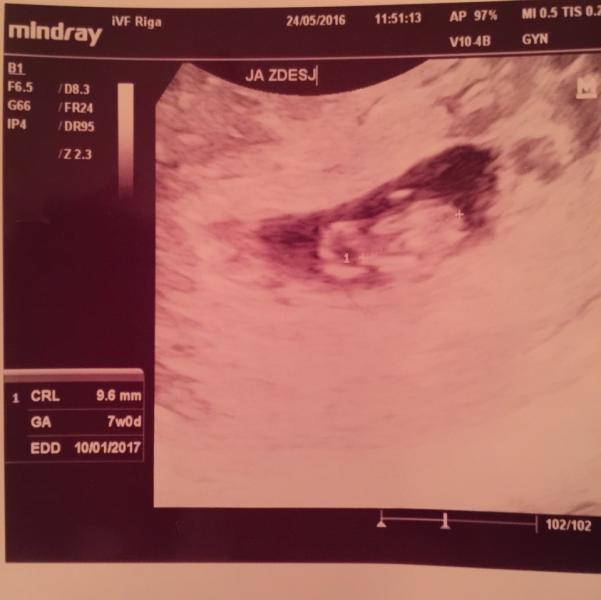

А мы сегодня были на первом узи:)) прижился только один малыш:( но он хорош,соответствует всем параметрам на 7 неделек:)) сердечко послушали(120 в минуту),как же это было волнительно!!! Черничка наша,расти здоровеньким,мы все тебя очень любим и ждем!!!!!!🤗🤗🤗🤗❤️👶